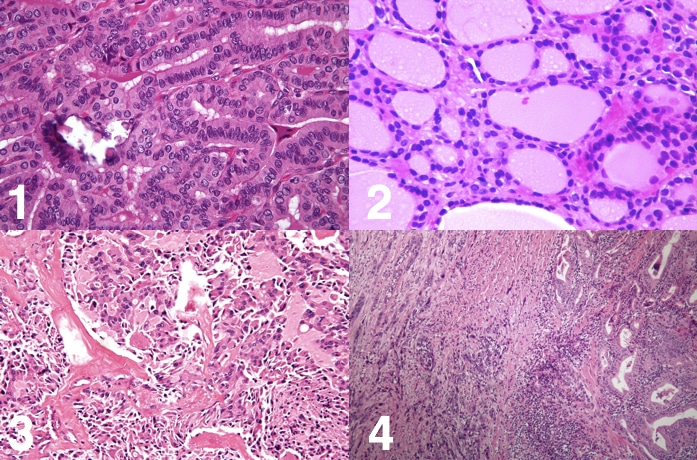

Diagnostic Strategies for Thyroid Nodules Based on

Diagnostic Strategies for Thyroid Nodules Based on